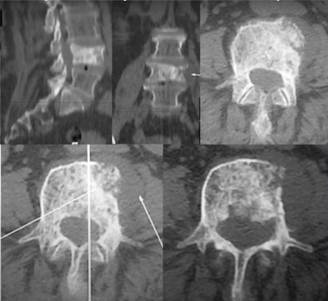

Проводиться індивідуально до кожного випадку захворювання. Онкологічні процеси що розвиваються з кісткових тканин хребця нерідко призводять до компресії прилеглих структур, а саме спинного мозку, нервових корінців, з розвитком неврологічної симптоматики. Нейрохірургічне видалення пухлини це хоч і невіддільна, але лише частина лікування.

У нейрохірургічному відділенні з 2020 року введено новий метод хірургічного лікування пухлин хребта та спинного мозку. Він полягає у введенні в стегнову артерію пацієнта спеціального провідника, який під апаратом ЕОП по судинах підводиться до судин які кровопостачають пухлину.

Після цього ці судини емболізують, тобто перекривають їх просвіт, в результаті чого пухлина втрачає своє живлення, і надалі, вже при хірургічному видаленні цієї пухлини число крововтрати зводиться на самий мінімум, що скорочує і час операції, і знижує розвиток масивної кровотечі та розвитку геморагічного шоку.